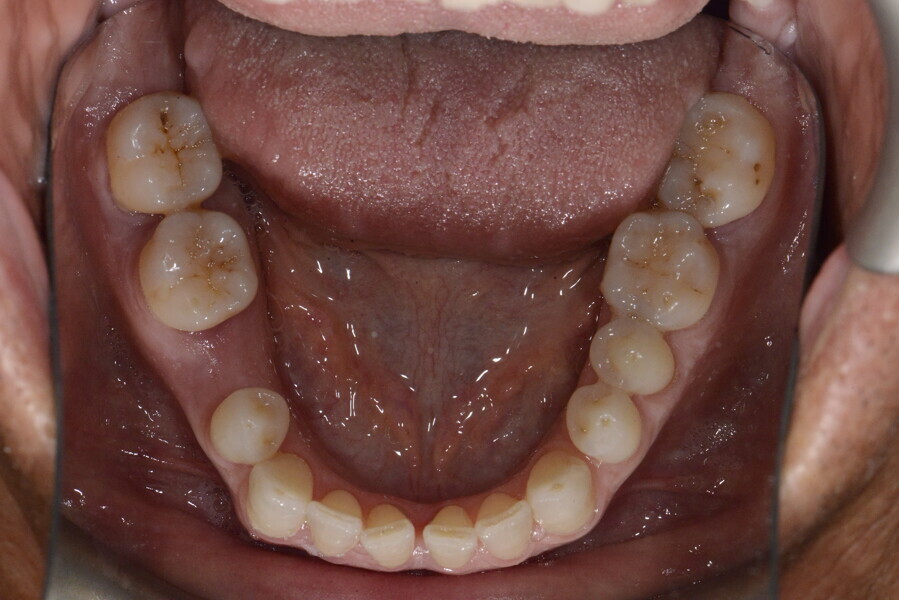

The 58-year-old patient wished to improve his oral aesthetics and function, complaining of mobility of the posterior teeth and wear of the anterior teeth. After data collection, a very complex situation was identified (Figs. 11–13):

1. severe periodontitis with poor prognosis of some teeth;

2. anterior crossbite;

3. severe wear mainly of the anterior teeth and compensatory eruption;38

4. atypical swallowing and lower posture of the tongue at rest;

5. masticatory dysfunction during the mastication test; and

6. no significant signs of temporomandibular disorder.